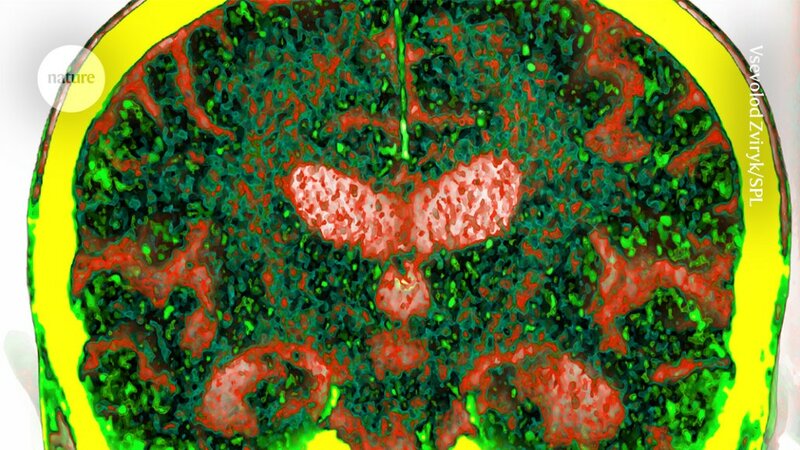

Early dementia diagnosis: blood proteins reveal at-risk people